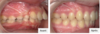

Les dents vue de profil avant et après traitement appareil multi-attaches